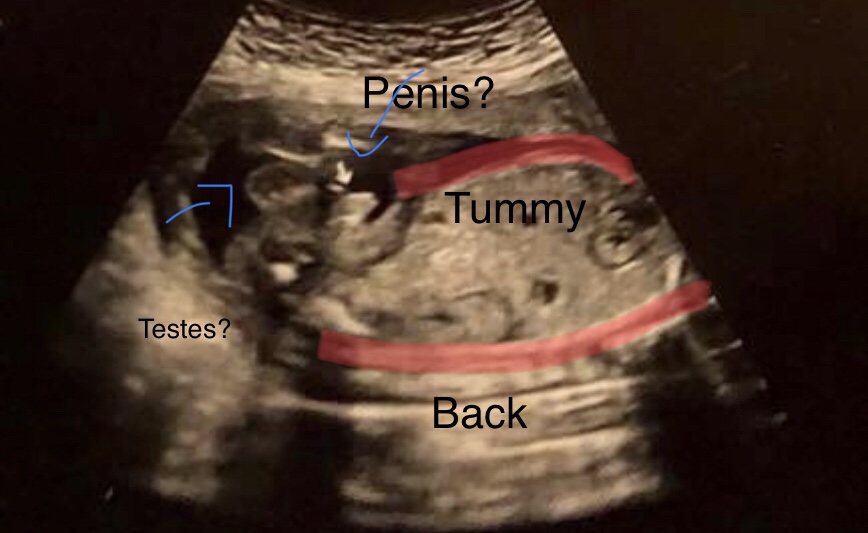

I didn’t get a normal “potty shot” but does ths definitely look like it’s a penis?

Tried to label what I think they were seeing if that makes sense lol

Mommy3boyz lol, I think what you labelled as testes is the leg? Remember the testes don’t descend until after birth. What appears to be boy parts may actually be the umbilical cord?

It’s a hard one to tell. If anything I’d think the baby’s parts are where the right arm of the lower arrow is pointing, if that makes sense?

I think you’re right about the leg haha I was thinking about that after I labeled it that it didn’t look quite right! I think the penis looks like it could be right only because there looks to be a little opening at the tip of it but I’m not quite sure lol.

This was the only gender shot I got unfortunately! She said it’s a boy, and that was the picture. The very top pic you can see it says boy in the left corner there, that’s what she was showing us there’s the little white arrow pointing at the “penis”